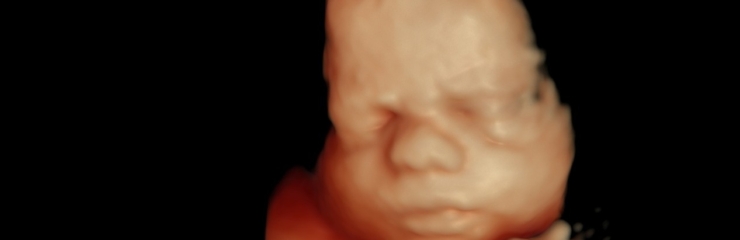

Kaelalülid on selgelt nähtavad. 23. nädalal kaalub loode umbes 550 grammi. 23. nädalast on hea visualiseerida 4D ultraheliuuringu käigus loote näojooni.

24. nädalal on loode umbes 30 sentimeetri pikkune ja kaalub umbes 650 grammi.

- Soovi korral 4D ultraheliuuring (24.–32. nädal)

Loote kaal on umbes 1 kilogramm ja ta on 35 sentimeetri pikkune. See on parim aeg 4D ultraheliuuringu käigus loote näo vaatamiseks.